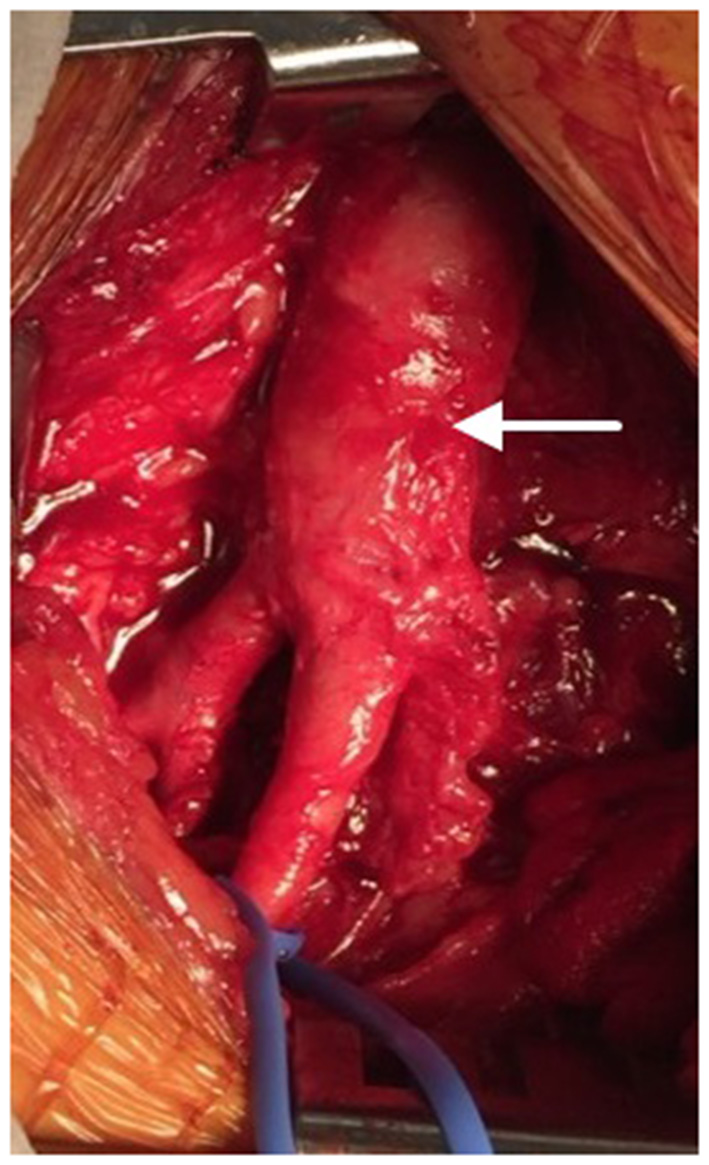

The regenerative potential of SIS-ECM when used in patch angioplasty is demonstrated through histology from a complicated case showing successful integration of the SIS-ECM patch into site-appropriate endarterectomized vessel tissue. A 55-year-old Caucasian male underwent right CFA endarterectomy with patch angioplasty using a SIS-ECM patch (Figures 1, 2) with no subsequent adverse events. Sixteen months later, due to disease progression at a distal adjacent site, an additional operation was performed. The previously placed SIS-ECM patch in the right CFA was found to be grossly indistinguishable from the surrounding endarterectomy site arterial tissue. At this surgery, the patch could be identified only by the presence of the polypropylene sutures used for the initial repair (Figures 1, 3). An additional endarterectomy and vascular reconstruction were performed with another SIS-ECM patch, extending the previous patch. On follow-up, the patient did well, with unremarkable non-invasive testing.

Figure 2

Initial patch angioplasty of the common femoral artery using an SIS-ECM patch (arrow) following endarterectomy.